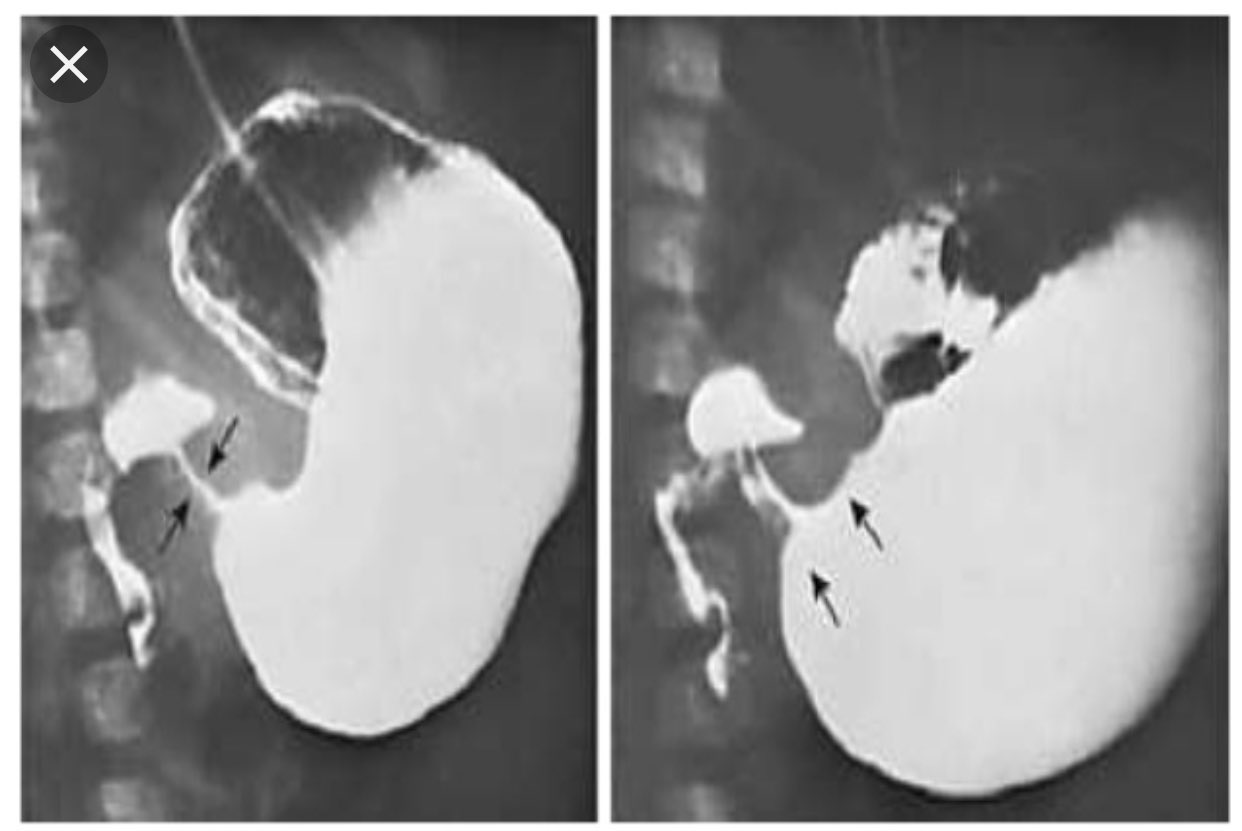

Pyloric Stenosis Upper Gi Series Weight Gain After Pyloric Stenosis Surgery some infants experience poor feeding and weight loss, but others demonstrate normal weight gain. a baby with pyloric stenosis often forcefully vomits since formula or breast milk can’t leave their stomach. in general, patients who receive surgical treatment for pyloric stenosis have an excellent recovery and very few suffer any. true recurrent hypertrophic pyloric stenosis (rps). Weight Gain After Pyloric Stenosis Surgery.

From www.jpedsurg.org